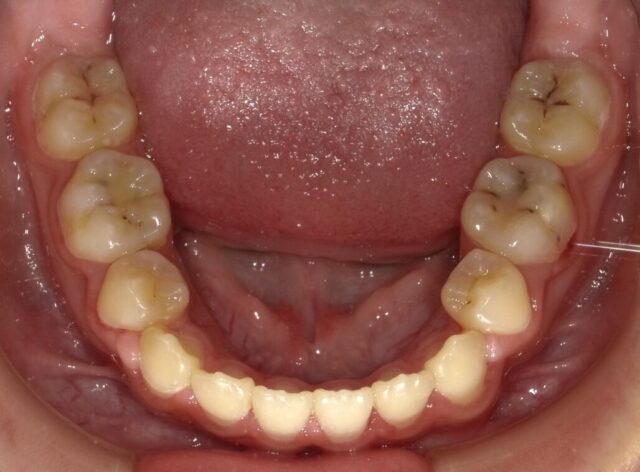

≪下顎咬合面観≫

2023年5月

2023年6月

2023年7月

2023年8月

2023年9月

2023年10月

2023年11月

2023年12月

2024年1月

2024年2月

2024年3月

2024年4月

2024年5月

2024年6月

2024年7月

2024年8月

2024年9月

2024年10月

2024年12月

2025年1月